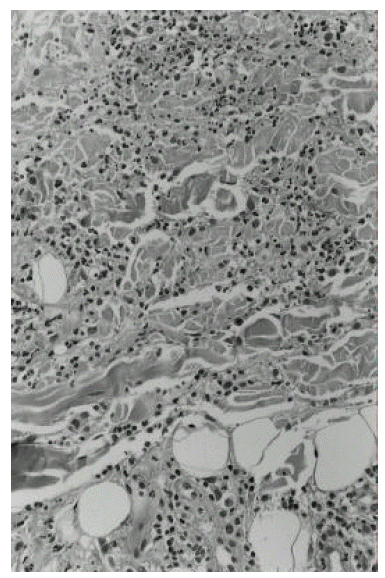

The clinical course of the patient is summarized in Figure 1. Induction therapy with ATRA was initiated at a dose of 70 mg/day (45 mg/m2/day). On the 4th day from the start of ATRA, white blood cell count increased up to 28.3×109/L and chemotherapy with idarubicin (12 mg/m2/day for 3 days) and cytarabin (100 mg/m2/day for 7 days) was instituted. On day 24, multiple painful erythematous plaques appeared on both cheeks, right wrist and both shins and the temperature rose to 40°C. At that point, her white cell count was 2.5×109/L, with 80% neutrophils and 0% blasts. All blood cultures and urine cultures were negative; her chest X-ray was unremarkable. Skin biopsy was performed from both cheeks and left shin, which revealed a dermal infiltrate of mature neutrophils and subepithelial edema (Figure 2). There was no fibrinoid necrosis or intramural cellular infiltrate suggesting vasculitis.

Figure 2.

A skin biopsy specimen from left shin. It shows a diffuse dense dermal infiltrate of neutrophils. No leukemic cells or microorganisms are present.